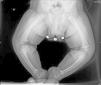

Se presentan 2 casos clínicos de niños con raquitismo carencial. Caso 1: niña de 20 meses remitida a las consultas de Traumatología y Pediatría por genu varo. En cuanto a sus antecedentes, sus padres proceden de Marruecos, recibía lactancia materna y presentaba diversificación alimentaria no reglada. No toma profilaxis antirraquítica y escasa exposición solar. Desarrollo ponderoestatural y psicomotor correctos. En las pruebas complementarias destacan: hormona paratiroidea intacta (PTH-i) de 406pg/ml; calcio de 9,4mg/dl; magnesio de 2,2mg/dl; fosfato de 4mg/dl; fosfatasa alcalina de 649U/l y 25-hidroxicolecalciferol (25-[OH]) vitamina D de 6ng/ml (15 a 60ng/ml). En la radiología se observan el ensanchamiento y la irregularidad de las metáfisis del fémur distal y la tibia proximal y distal, con marcado aumento de la incurvación de la tibia bilateral. Las metáfisis tibiales se encuentran deformadas, con el borde afilado en los extremos mediales. Las metáfisis distales del cúbito y el radio son irregulares (fig. 1). Caso 2: niño de 8 meses de origen magrebí que acude a Urgencias por crisis comicial. En la analítica se detectan un calcio de 5,3mg/dl, magnesio de 1,6mg/dl y fosfato de 3,6mg/dl. Había recibido lactancia materna exclusiva hasta los 6 meses y no toma profilaxis antirraquítica. Radiográficamente se observa un agrandamiento de las metáfisis del fémur, húmero y radio en forma de copa, con desflecamiento metafisario (fig. 2). Al completar el estudio analítico encontramos una PTH-i de 463pg/ml y 25-(OH) vitamina D de 8,3ng/ml. En ambos casos se indica tratamiento con vitamina D, ingesta adecuada de calcio y exposición a la luz solar, con buena respuesta y evolución.